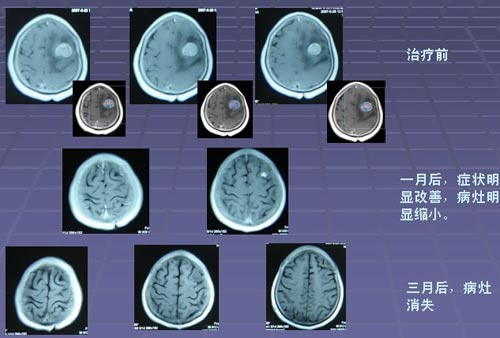

肺癌脑转移五年生存率

在大多数人的意识里,癌症就代表着绝望与死亡。但据中国工程院院士、中国医学科学院肿瘤医院孙燕教授2011年介绍:肿瘤科医生患癌后, 80%都得到了治愈(5年生存)特别是一些发生 肺癌脑转移 ,目前依然带瘤生存。。而国家癌症中心全国肿瘤防治研究办公室 ...